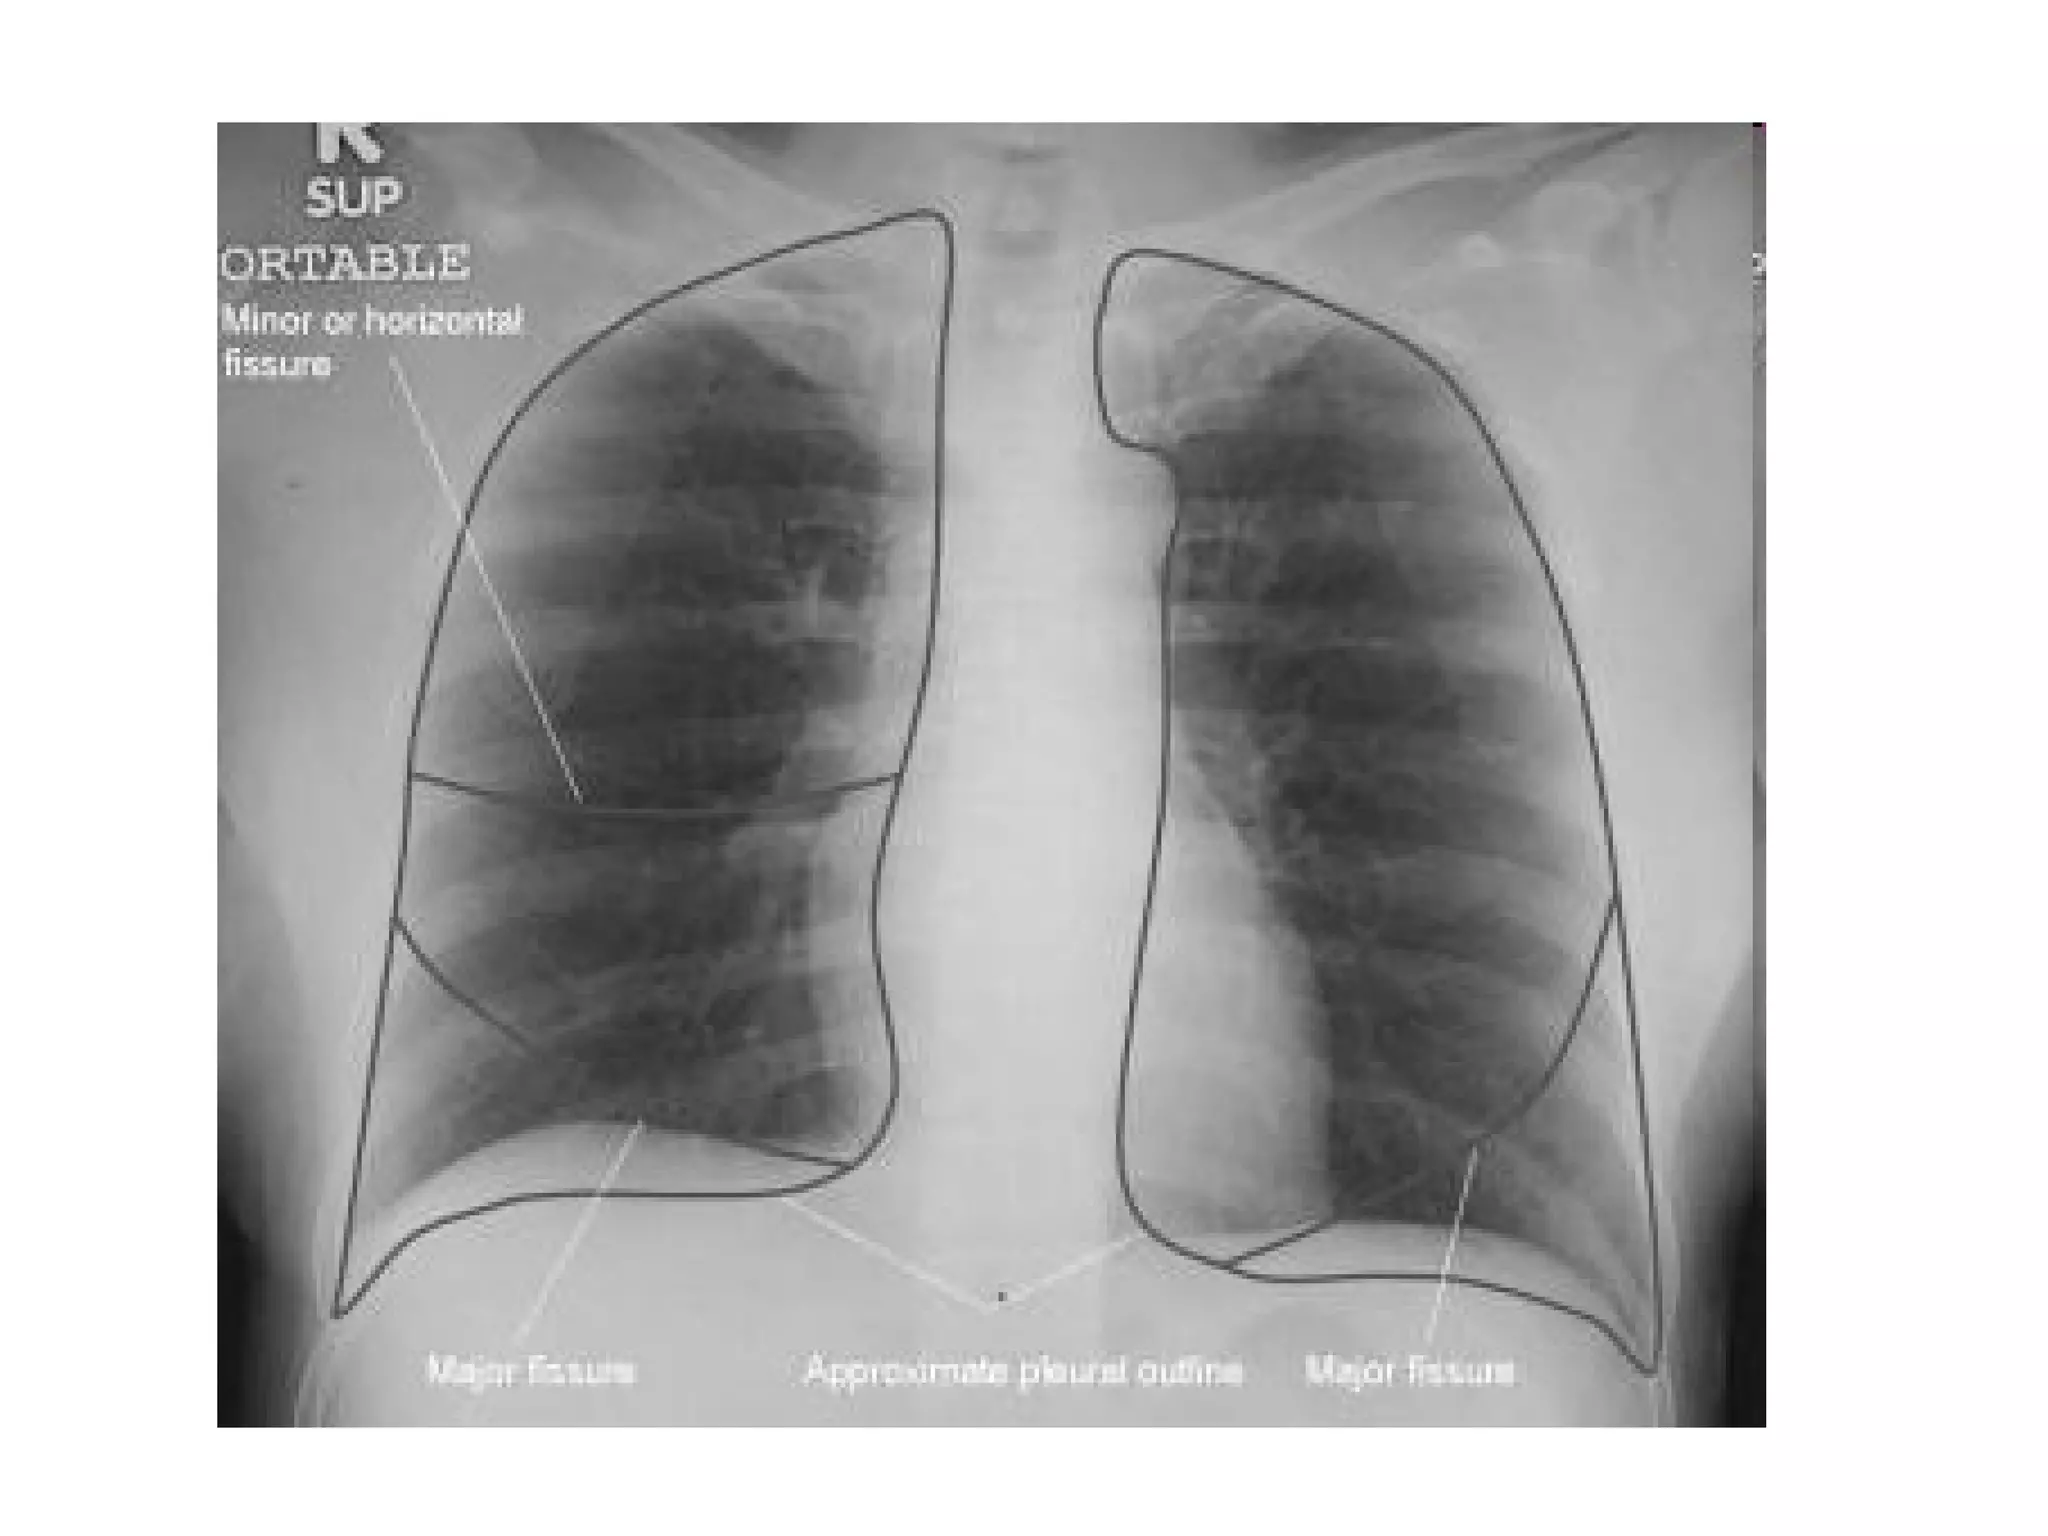

The fissures

The main fissures

The horizontal fissure is seen often incompletely

on PA film

The oblique fissures are seen on lateral film

commence posteriorly at the level of T4 or T5

passing through the hilum. The left is steeper

and finishes 5cm behind the anterior

costophrenic angle, where as the right ends just

behind the angle.

Accessory fissures, the azygos fissure is

comma shaped and nearly always right sided.

Right Oblique

Fissure

Horizontal

Left

Oblique

RUL

LUL

RML

RLL

LLL

Azygos

The fissures The mainfissures The horizontal fissure is seen often incompletely on PA film The oblique fissures are seen on lateral film commence posteriorly at the level of T4 or T5 passing through the hilum. The left is steeper and finishes 5cm behind the anterior costophrenic angle, where as the right ends just behind the angle. Accessory fissures, the azygos fissure is comma shaped and nearly always right sided.

Right Oblique Fissure Horizontal Fissure Left Oblique Fissure

RUL LUL RML RLL LLL